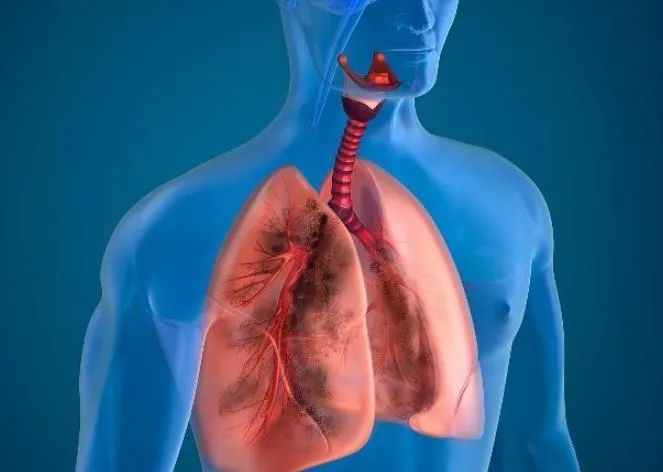

肺栓塞(pulmonary embolism,PE)是内源性或外源性栓子阻塞肺动脉引起肺循环障碍的临床和病理生理综合征,包括肺血栓栓塞症、脂肪栓塞综合征、羊水栓塞、空气栓塞、肿瘤栓塞和细菌栓塞等。

肺血栓栓塞症(pulmonary thromboembolism,PTE)是指来自静脉系统或右心的血栓阻塞肺动脉或其分支所致疾病,以肺循环(含右心)和呼吸功能障碍为主要临床表现和病理生理特征,是最常见的肺栓塞类型,通常肺栓塞即指 PTE。

深静脉血栓形成(deep venous thrombosis,DVT)是引起 PTE 的主要血栓来源,DVT多发于下肢或者骨盆深静脉,脱落后随血流循环进入肺动脉及其分支,PTE 常为 DVT 的合并症。

上面廖阿姨的肺栓塞就属于肺血栓栓塞,来源于静脉,所以能用溶栓或抗凝的方式“化”掉。